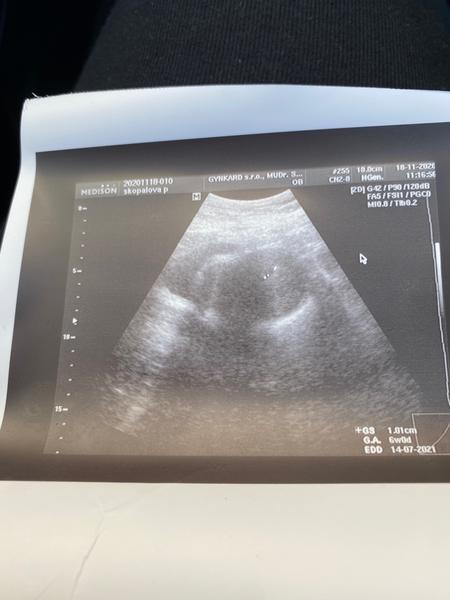

33. DC a na UTZ pouze dutinka 3 mm. Mohla být ovulace později?

33 DC a na UTZ pouze 3mm dutinka. Mohla být ovulace později? Cyklus pravidelný 28 dní. Mammatest 10 jasně pozitivní i odpoledne. Stalo se někomu?

@pepickovapavlinka ale 1.1 cm. Já 3mm